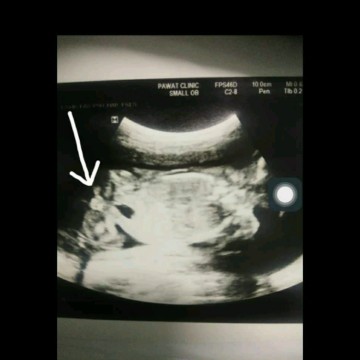

บ้านไหนมองออกบ้างคะ ว่ากลีบหรือจู๋ ? อันนี้ไปตอน 15 week รอซาวใหม่อีกรอบคะเพื่อความมั่นใจ ??

มุมนี้ใช่หว่างขาน้องใช่ไหมคะ?